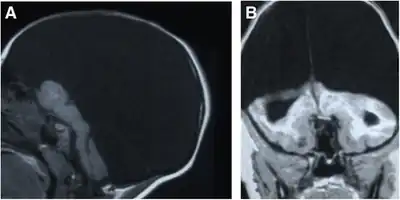

| a,b)MRI performed on individual affected by hydranencephaly | |